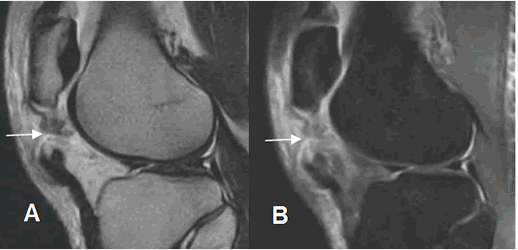

Fig 152. Ruptura parcial del tendón patelar.

A: RM sagital en T1, B: RM sagital en T2 y C: RM sagital en STIR. Alteración de la señal del tendón patelar en su tercio distal siendo hipointenso en T1 e hiperintenso en T2 y STIR. (Flechas delgadas). Está adelgazado y con ruptura de algunas fibras en la parte posterior, con escaso líquido asociado. (Flechas gruesas).